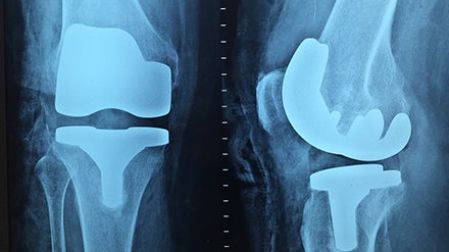

-¿Por una fractura expuesta se puede contraer una infección que ponga en riesgo la vida?

R= Esto es verdad, las fracturas expuesta son una causa de riesgo, incluso de muerte, son las urgencias primordiales en la ortopedia y deben ser atentidas lo más pronto posible.